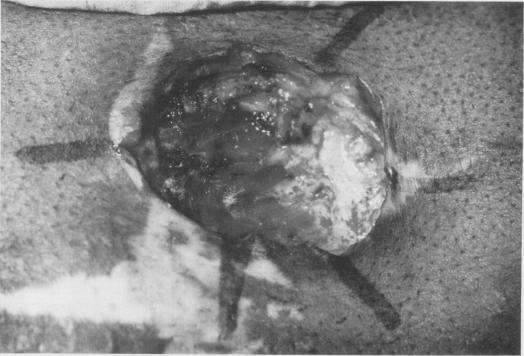

Ten patients with dermatofibrosarcoma protuberans, all of whom had been treated previously by conventional excisional surgery without success, were treated with Mohs micrographic surgery. A team approach utilizing margin control by Mohs-trained physicians and reconstruction by surgical specialists was employed. Average follow-up exceeds 3 1/2 years, with no recurrences. Microscopically controlled excision appears to be the treatment of choice for dermatofibrosarcoma protuberans.

10例隆突性皮肤纤维肉瘤患者,之前均接受过传统切除手术但未成功,现采用莫氏显微外科手术进行治疗。采用了一种团队协作方法,由接受过莫氏手术培训的医生进行切缘控制,并由外科专家进行重建。平均随访时间超过3年半,无复发情况。显微镜控制下的切除术似乎是隆突性皮肤纤维肉瘤的首选治疗方法。